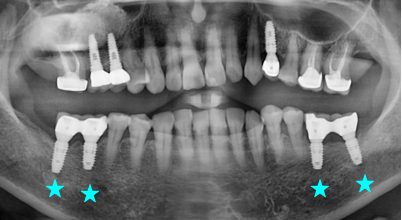

Internal Bone Level - Tapered

The IB-T implant system offers a flexible solution for all indications and esthetic outcomes. It is a submerged type implant that has an internal hex 11˚ taper connection. With tapered body design, it allows excellent primary stability, and it can be applied to any situation as it has various diameters, lengths and prosthetic line-up.